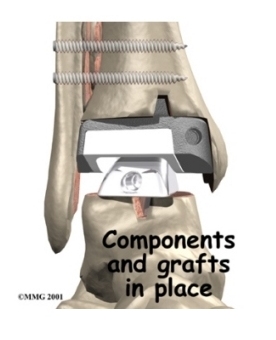

The artificial ankle

Each artificial ankle prosthesis is made of two parts:

- The tibial component is the part of the artificial joint that replaces the socket portion of the ankle (the top section).

- The talus component replaces the top of the talus.

The tibial component is usually made up of two parts: a flat metal piece called a metal tray that is attached directly to the tibia bone, and a plastic cup that fits onto the metal piece, forming a socket for the artificial ankle joint. The talus component is made of metal and fits into the socket of the tibial component.

Your surgeon may use a special type of epoxy cement to attach the metal components to the bone. This is called a .

Some surgeons prefer to put the new joint in without using cement. This is called an . The surface of this type of prosthesis bears a fine mesh of holes that allow bone to grow into the mesh and attach the prosthesis to the bone.